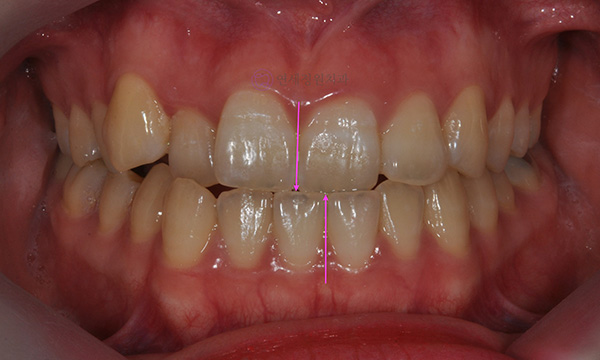

위 환자분은 치아 중심선이 맞지 않는다는 주소로 치과에 내원하셨습니다. 미소시 사진을 보면 위 치아도 오른쪽(사진 상 왼쪽)으로 틀어져 있고, 아래 치아도 왼쪽(사진 상 오른쪽)으로 틀어져 있었습니다. 그리고 양쪽 입꼬리 근육의 활성도도 차이가 있어서, 웃었을 때 왼쪽 입꼬리가 오른쪽보다 덜 올라가서 비대칭이 더 강조되어 보였습니다.

치아 중심선의 차이를 개선하고, 얼굴의 중심과 치열의 중심을 맞춰주기 위하여 오른쪽 아래 작은 어금니를 하나만 발치하여 그 공간으로 아래 치열을 오른쪽으로 돌려주고, 위 치열은 전체적으로 왼쪽으로 치열을 이동시켜서 중심선을 맞추어 주었습니다.

위 아래 치아의 중심선이 일치하고 좌우 어금니의 교합도 잘 맞춰졌습니다. 좌우 입꼬리 올림근 활성도의 차이는 남아있음에도 얼굴의 중심과 위 아래 치아의 중심이 일치하여 미소시에도 교정 전보다 훨씬 자연스러운 미소를 짓게 되었습니다.